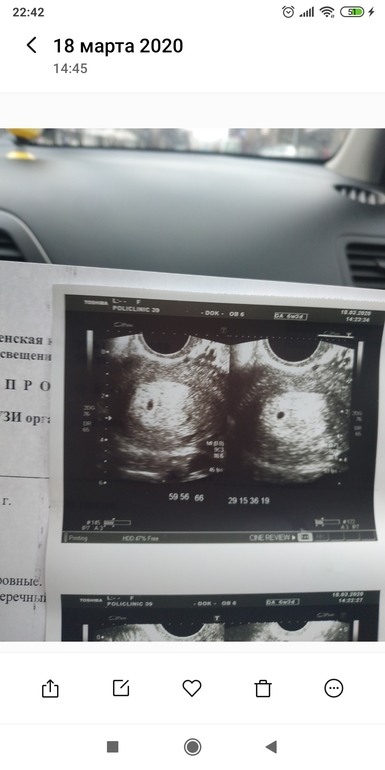

На первом снимке очень похоже на ПЯ. Диаметр 2,7 мм. Подождите несколько дней и переделайте в другом месте, яснее будет что и как

Easy, так там внизу снимка в углу написаны два диаметра которые она выставляла - это как раз два замера на снимке

1D 0,27mm

2D 0.26 mm

Easy, нет, условно говоря, один темный овал на первом снимке (пя) она замерила его диаметр как бы сверху овала и снизу, сверху это 1D, а снизу овала диаметр 2 D. В общем, 1 и 2 это порядковые номера замеров.

вот мои 2-3 недели эмбриональные были по узи. Пока отставить панику ХГЧ тут в районе 2000. Диаметр плодного 4,1 мм.

А ХГЧ сдавали? Я бы подумала, что это плодное яйцо. Просто только зарождается беременность

Москва

Похоже на плодное яйцо просто рано еще